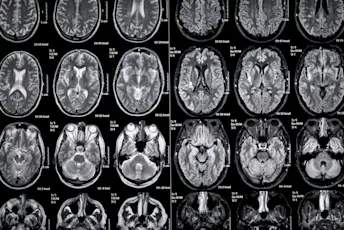

关于MS脑病变的6件事

他们是什么,如果可以防止,为什么治疗如此重要。